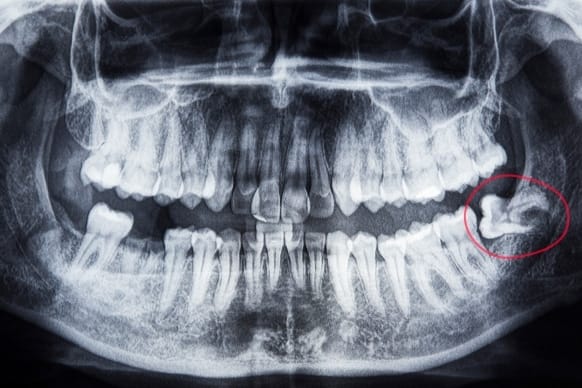

Third molars are also called wisdom teeth because they are the last set of adult teeth to appear in the mouth. Typically appearing between the ages of 17 and 21, many individuals face challenges due to insufficient space for these wisdom teeth, necessitating their removal. After wisdom teeth extraction surgery, most patients recover in 3–4 days, although complete recovery could take up to 7 days. If the extraction of an impacted wisdom tooth is complex and causes problems, the recovery period could be extended to around two weeks.

The wisdom teeth, or back teeth, erupt in your mouth last and farthest back, typically in your late teens or early 20s. This phase of mouth growth is typical. Two wisdom teeth in the upper jaw and two in the lower jaw make up the average set of four, although some people have more, fewer, or even none at all.

While some wisdom teeth pass through easily, some present challenges that may require extraction or other care.